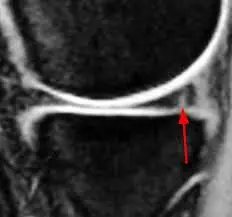

الطبيب هنا هو الشخص القادر على تحديد نوع القطع عبر التصوير بالرنين المغناطيسي (MRI)، لتحديد ما إذا كان يحتاج إلى تدخل جراحي أو يمكن علاجه بالعلاج الطبيعي.